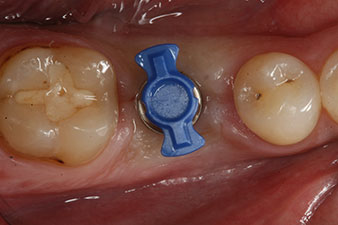

Фиг. 1: Първоначална клинична ситуация след зарастване на екстрахираната алвеола 36: Основата на костта е широка и има достатъчна кератинизирана гингива.

28-годишен пациент с анамнеза на тежък пушач е с екстрахиран 36 зъб в резултат на повторяем апикален пародонтит.

Поради почти незасегнатите съседни зъби, единственият начин за запълване на пространството е с имплант.